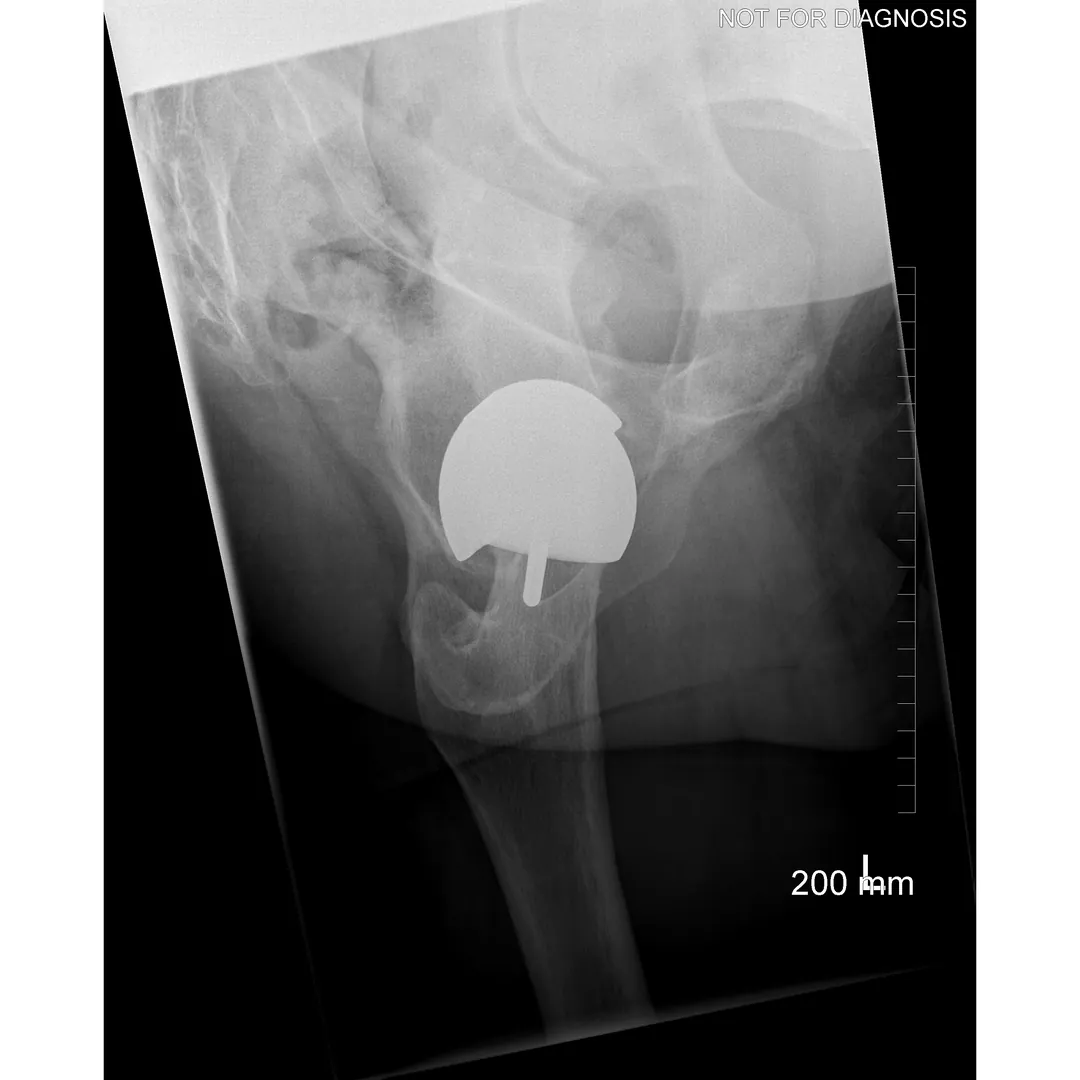

Hip resurfacing is a type of hip surgery used to treat hip arthritis, most commonly in younger and more active patients. Unlike a total hip replacement, hip resurfacing preserves more of your natural thigh bone. Instead of removing the entire femoral head (ball at the top of the thigh bone), the damaged surface is trimmed and covered with a smooth metal cap. The hip’s socket on the pelvis is also fitted with a metal cup.

Hip Resurfacing

- Preserves more natural bone (the femoral head is capped rather than replaced)

- Uses a larger ball size, which may reduce the risk of dislocation